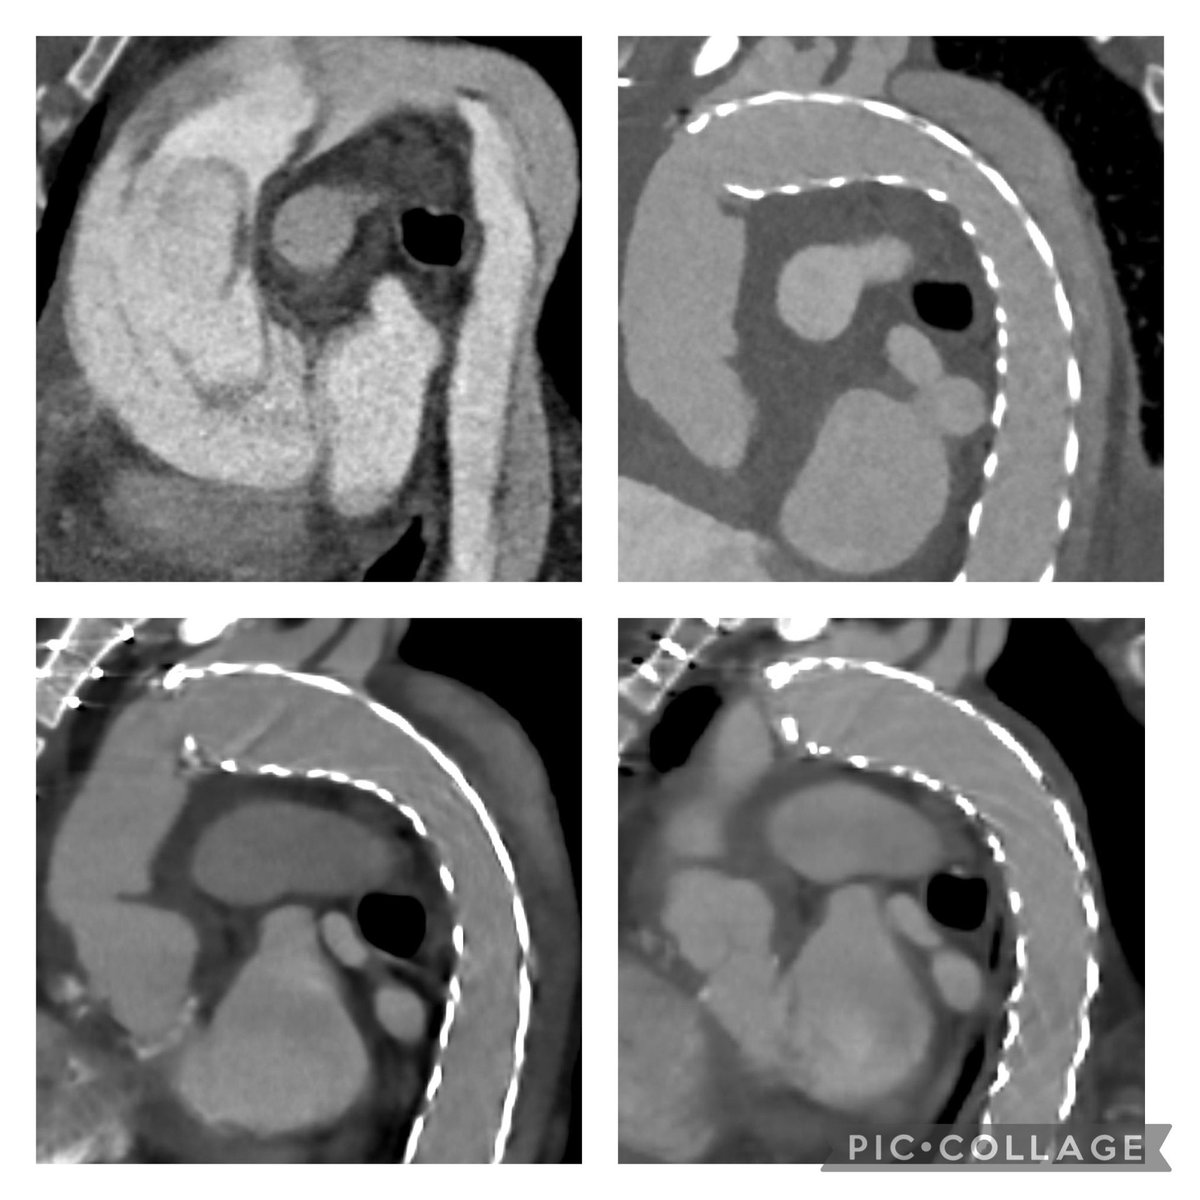

Challenge of the Week… Pectus Excavatum, Huge Aortic Aneurysm 85mm with Aortic Dissection, Aortic valve regurgitation, 51 y male, Ejection Fraction 20% Challenge: Chest Entry Extrathoracal CBP, On-X Bentall 25mm, Hemiarch

Challenge of the Week…

Pectus Excavatum, Huge Aortic Aneurysm 85mm with Aortic Dissection, Aortic valve regurgitation, 51 y male, Ejection Fraction 20%

Challenge: Chest Entry

Extrathoracal CBP, On-X Bentall 25mm, Hemiarch